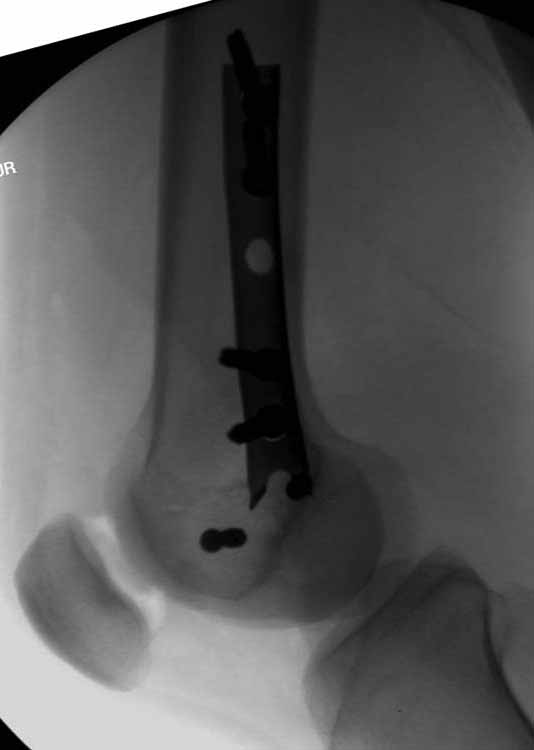

Ну зачем же так. Всё-таки считается "золотым стандартом". Во вложенном файле коллаж из сохранившихся фотографий одной из операций. Всё сделано закрыто и без ЭОПа.